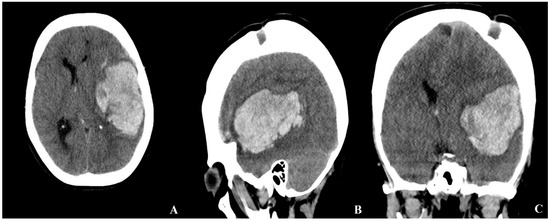

According to the history obtained from her husband, the patient had experienced a hemorrhagic stroke 15 years earlier, at which time MR angiography had confirmed the diagnosis of MMD, and she underwent multiple burr hole surgery (Figure 3 and Figure 4).

Figure 4. Three-dimensional brain CT reconstruction obtained 15 years after indirect revascularization, demonstrating the patient’s appearance following the multiple burr hole (MBH) procedure.